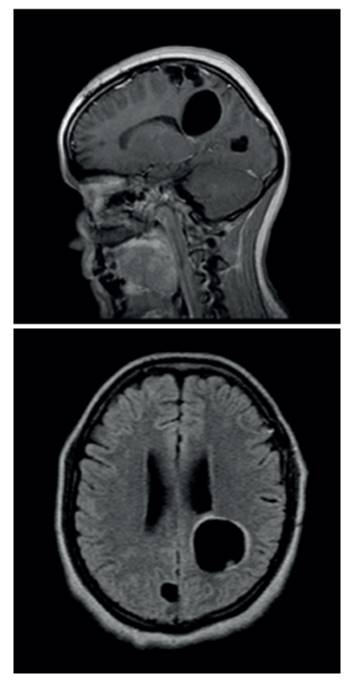

En la Imagen de RMN simple y contrastada (Figura 1) en secuencias de T1, se aprecian lesiones expansivas quísticas intraparenquimatosas cortico-subcorticales y periventriculares a nivel supratentorial; algunas de ellas con tejido interno compatible con neurocisticercosis. La lesión más prominente de tipo corticosubcortical frontotemporal izquierda, con contenido líquido no homogéneo y septaciones en su interior, con captación gruesa, intensa e irregular de su cápsula con discreto edema perilesional que desvía la línea media, colapsaba parcialmente el ventrículo lateral izquierdo y comprimía el tercer ventrículo. Razones por las cuales se decidió iniciar manejo con albendazol genérico, a dosis de 15 mg/ kg/día según lo establecido por el Centers for Disease Control and Prevention (CDC), asociado a medidas antiedema. Teniendo en cuenta el tamaño de la lesión, el compromiso motor y la desviación de la línea media, se decidió llevar a la paciente a drenaje quirúrgico de la lesión intraparenquimatosa fronto-parietal izquierda.

Figura 1 RMN contrastada en proyección sagital y axial, donde se observan lesiones que sugieren neurocisticercosis racemosa.